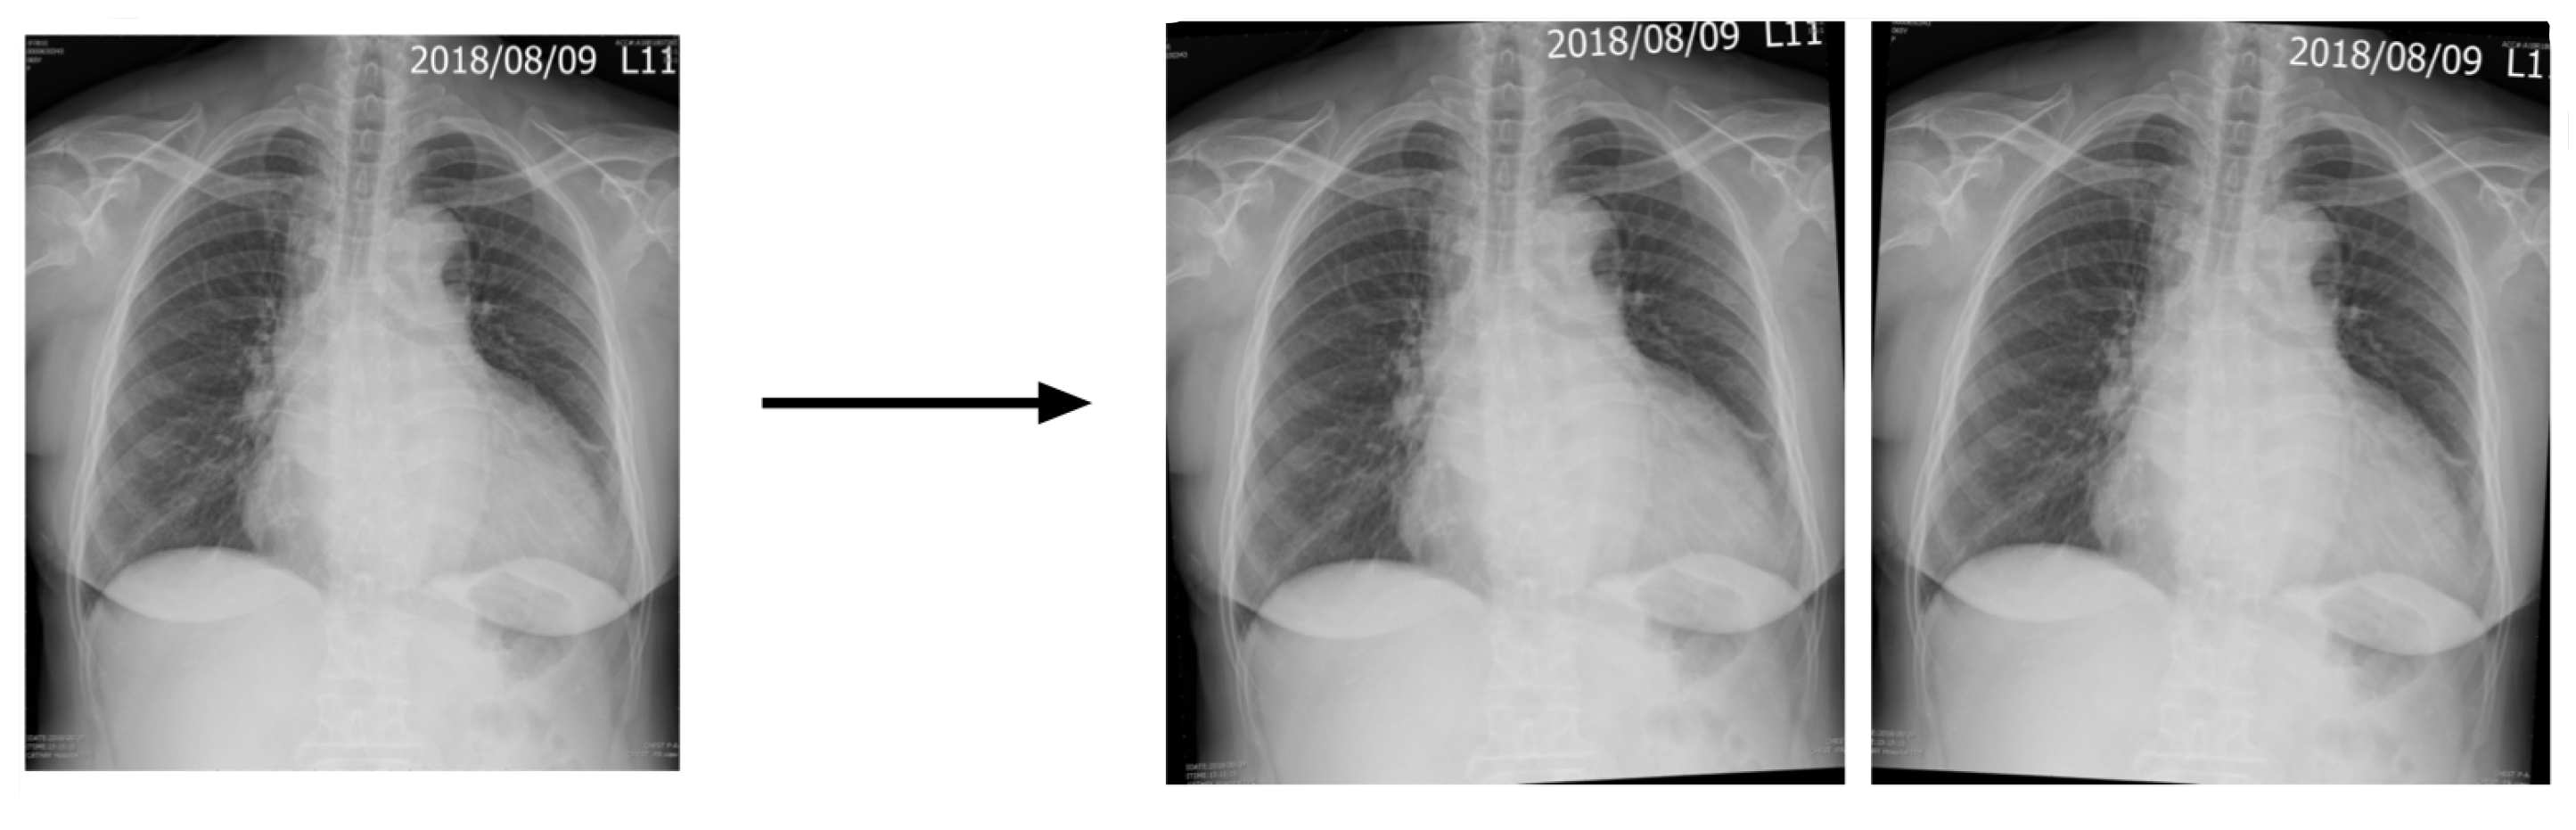

2.4. Image Enhancement

2.5. Data Augmentation